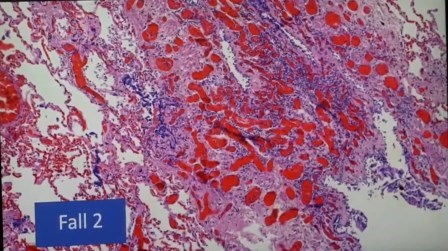

Eritrocitos grumos

Eritrocitos normales, separados

Otro caso de eritrocitos en grumos en inflamación de vena pulmonar

Infarto pulmonar que no debería ser mortal, se ven los linfocitos